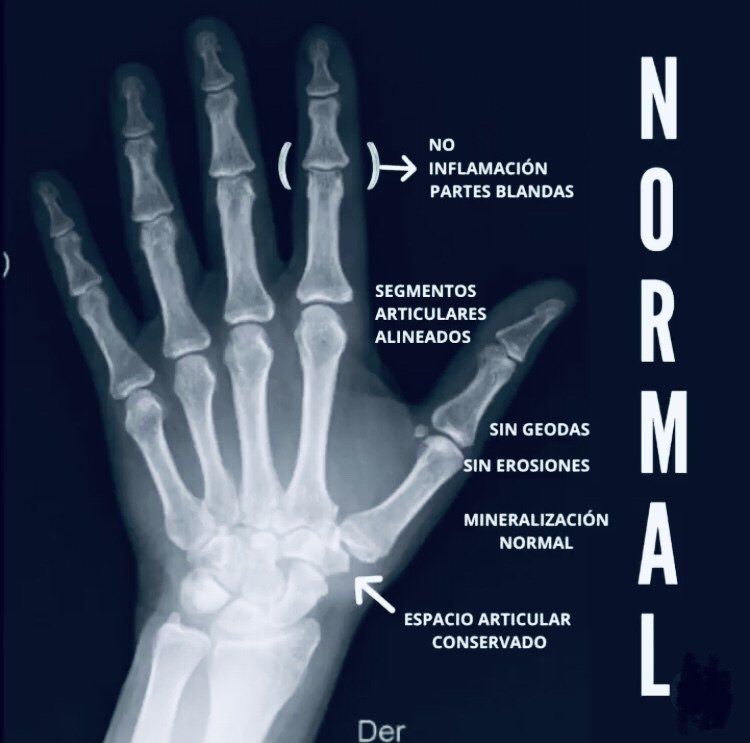

MANO NORMAL EN NIÑO Y ADULTO

En la primera radiografía se puede ver una mano normal de adulto donde se aprecia la ausencia de inflamación, la correcta alineación de las articulaciones, una mineralización normal y los espacios interarticulares conservados.